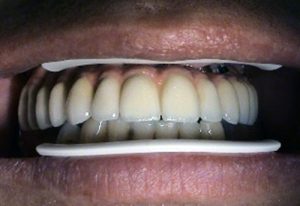

– "teeth in one day"- "all in one" – implantation and

provisional prosthetics during one day

– "all on four"

"all on six" – implant solution concept for complete

tooth loss of upper or lower jaw supported by four or six

implants